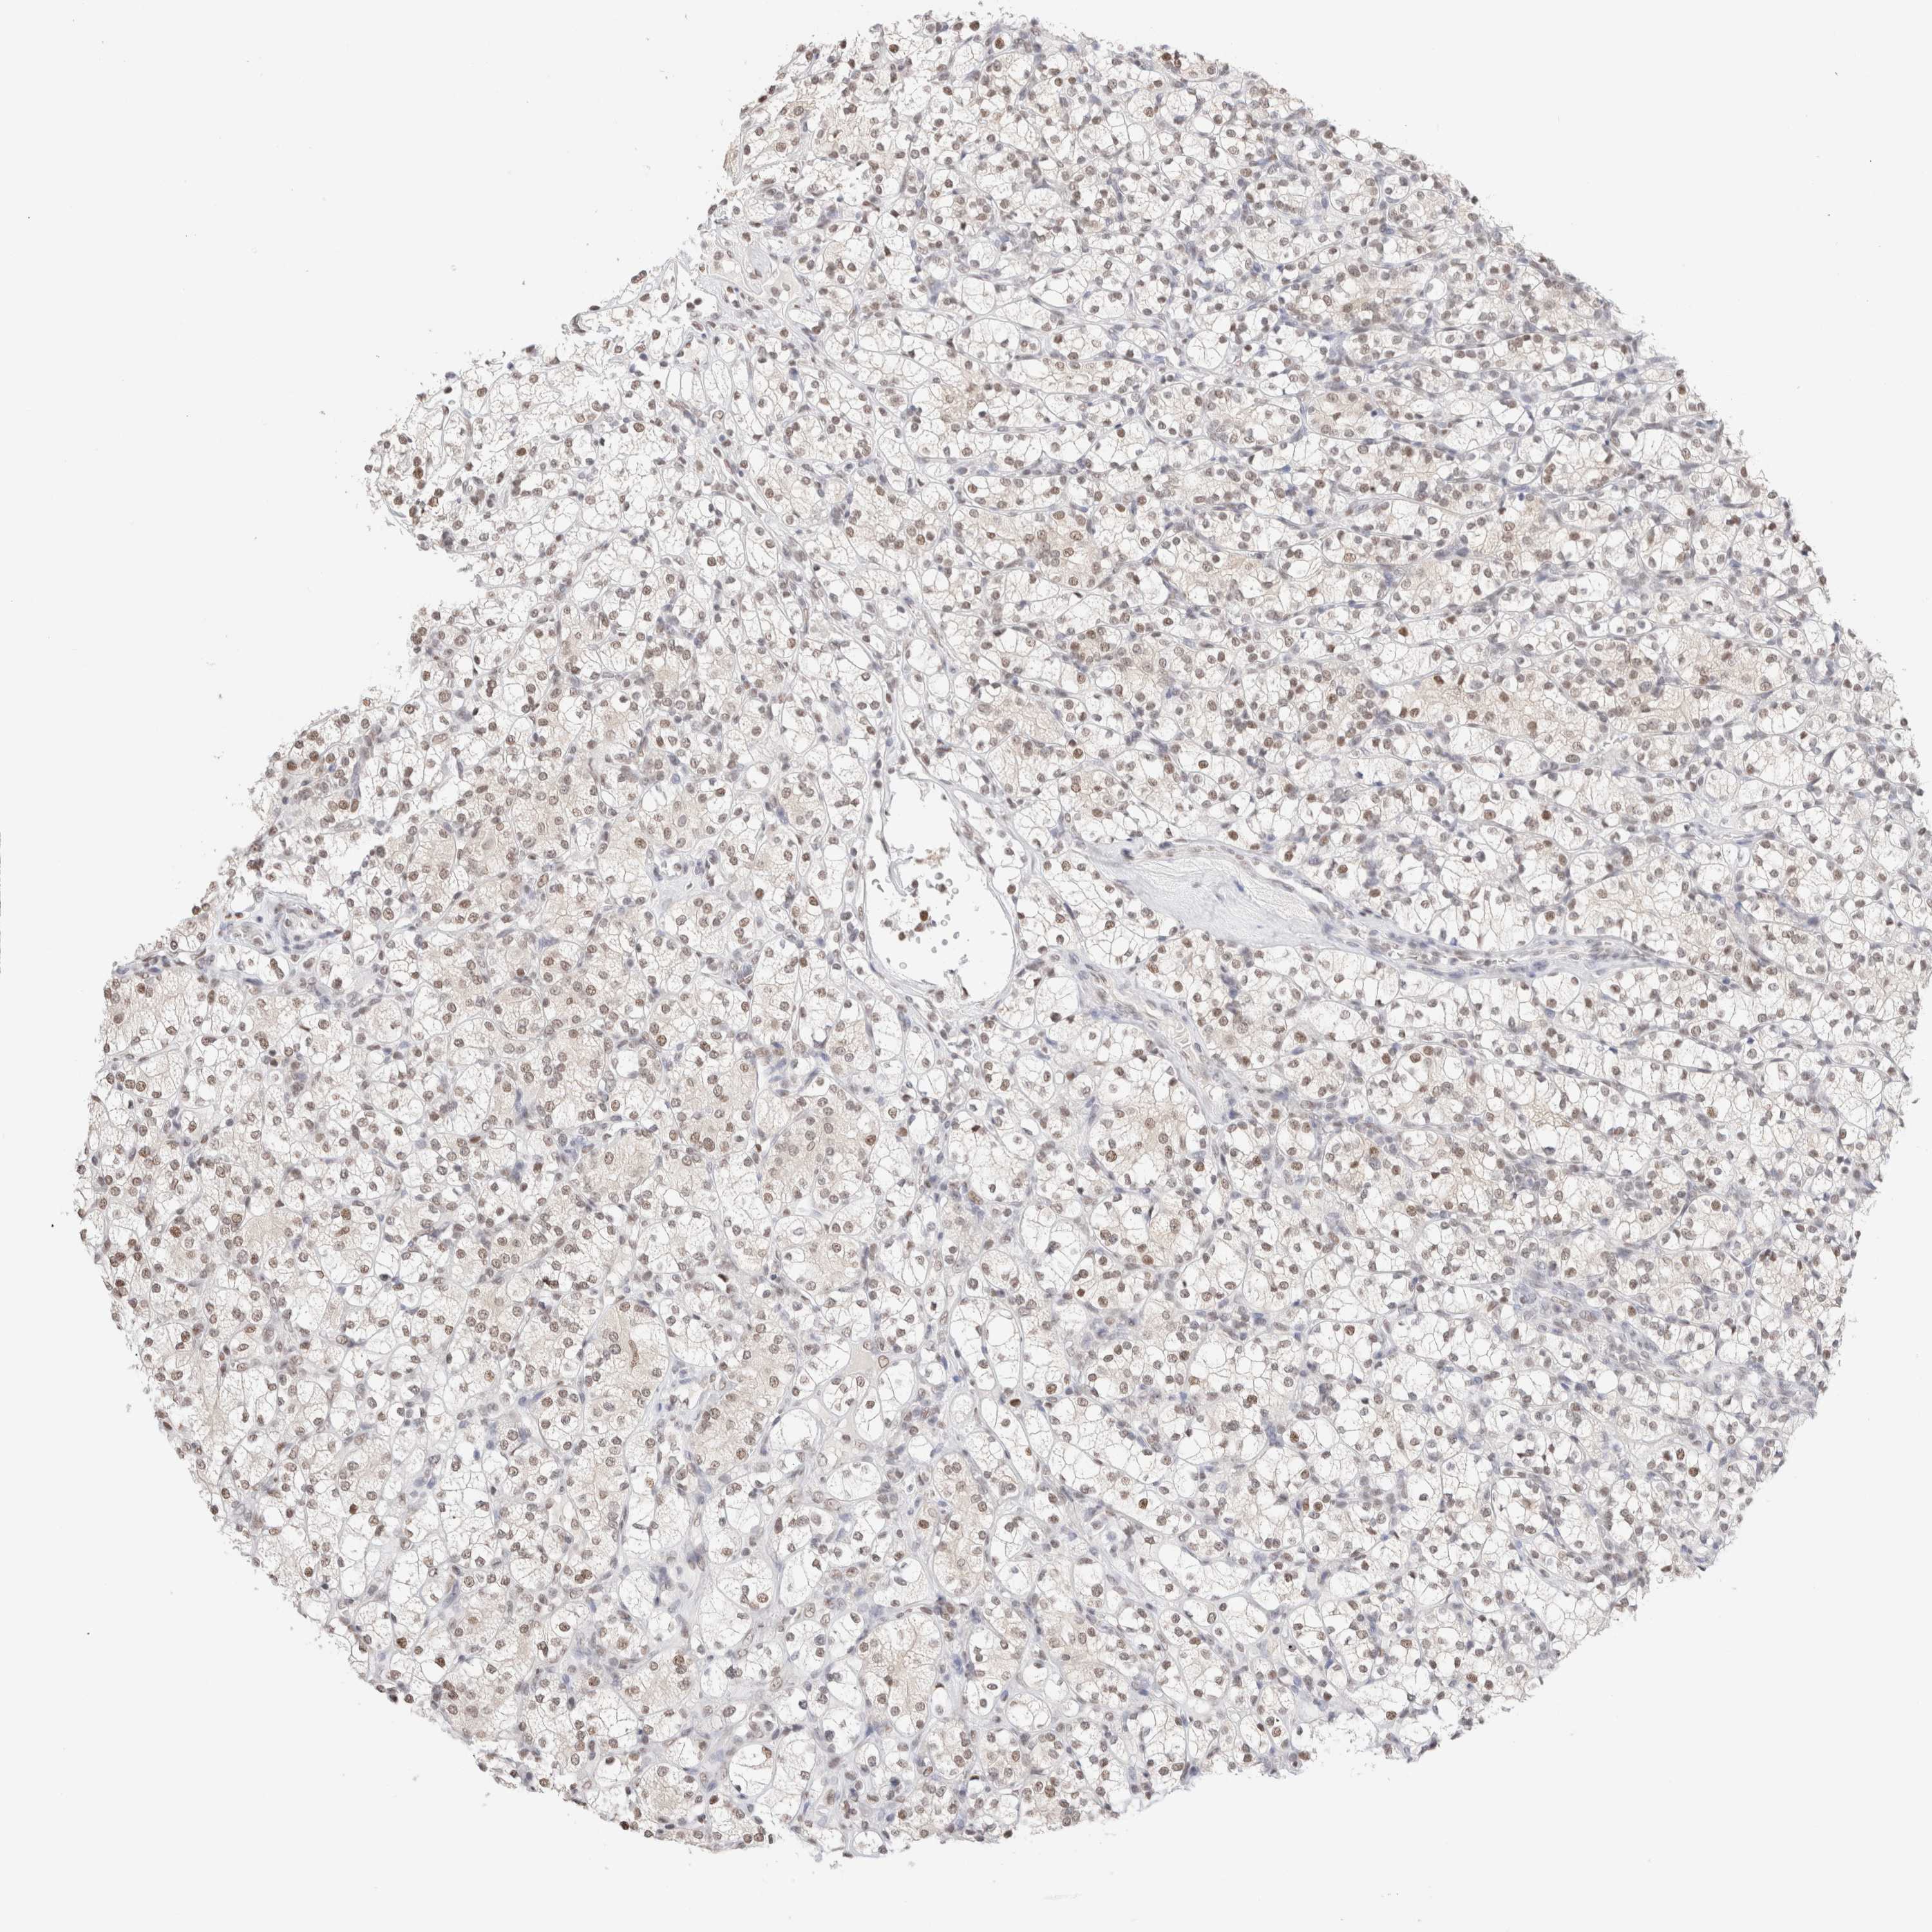

KIDNEY RENAL CLEAR CELL CARCINOMA (TCGA) - Interactive survival scatter ploti

SUPT3H is not prognostic in Kidney Renal Clear Cell Carcinoma (TCGA)

: 4.7

Average pTPM 3.5

Number of samples 521